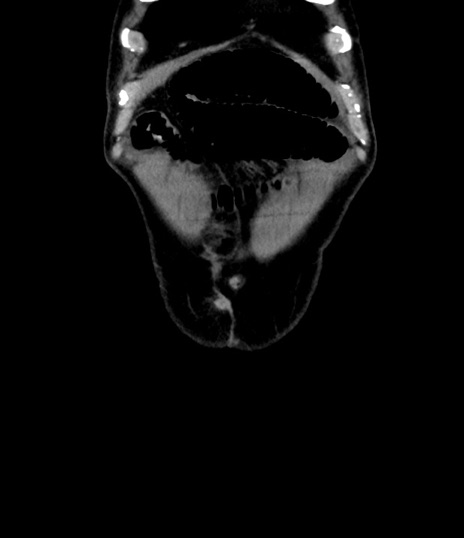

症例8(冠状断像)

【症例】 60歳代男性

【主訴】 黒色吐物

【現病歴】 4日前から嘔気自覚、2日前の朝食後にも嘔気あり、自分で手で嘔吐反射起こし嘔吐したところ血が混ざっていたため受診。

【既往歴】 5年前汎発性腹膜炎を伴う急性虫垂炎で手術、高血圧、前立腺肥大症、高脂血症

【身体所見】 腹部正中に手術癩痕あり 腹部平坦・軟圧痛なし膨満感あり

【データ】WBC 8400、CRP 4.54